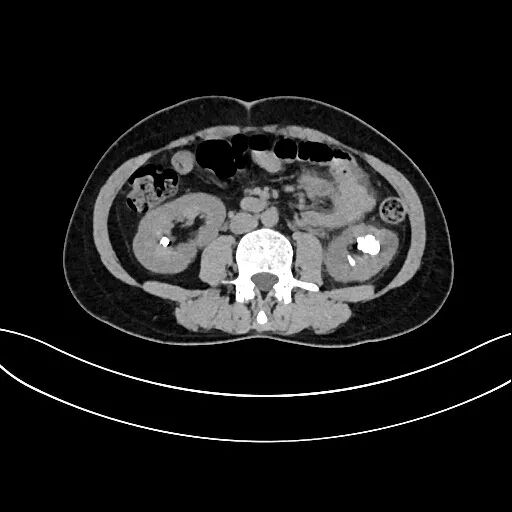

值班醫(yī)生楊輝接診后,急查CT提示,張女士左側(cè)輸尿管多發(fā)結(jié)石,雙腎多發(fā)結(jié)石?!盎颊弋?dāng)時(shí)是因?yàn)樽筝斈蚬芙Y(jié)石引起泌尿系感染,血、尿化驗(yàn)均提示其為重度感染,病情十分危重。”楊輝說(shuō)。

張女士的結(jié)石既大又多,左側(cè)輸尿管結(jié)石為1cm,左腎輸尿管連接處結(jié)石為1.5cm,左腎上盞結(jié)石為2cm,左腎下極結(jié)石為2cm。一般結(jié)石在1cm以上就已經(jīng)很大了,而張女士單左腎結(jié)石就有4處,每處都超過(guò)了1cm,而且引起了嚴(yán)重的感染。右側(cè)腎臟也有2cm大小結(jié)石。

“其他結(jié)石倒比較普通,但左腎下盞以及右腎結(jié)石卻不是普通的腎結(jié)石?!敝魅螐堷櫼阍诹私鈴埮康牟∏楹蟊硎荆胀ǖ哪I結(jié)石位于腎盂內(nèi),而張女士的結(jié)石包埋于腎髓質(zhì)內(nèi),這是一種罕見(jiàn)的髓質(zhì)海綿腎引起的腎髓質(zhì)結(jié)石。